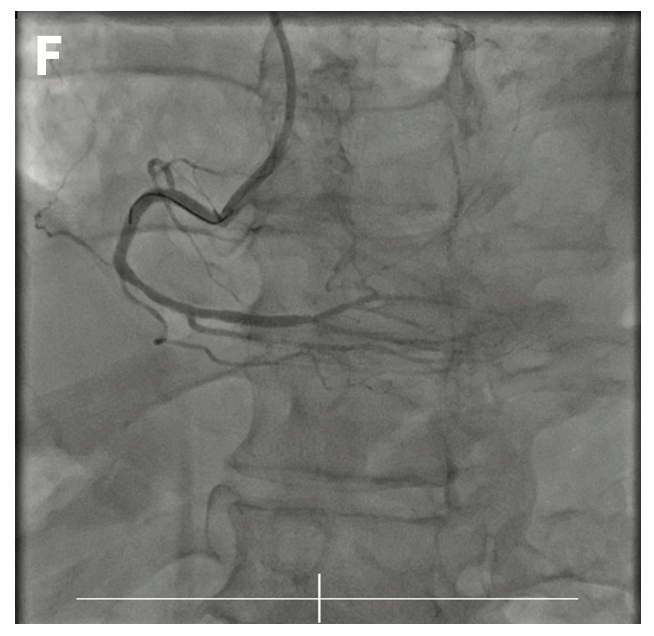

A 70-year-old male was diagnosed with three-vessel disease:

• 90% occluded left anterior descending artery (LAD);

• 70% occluded left circumflex artery (LCx); and

• 100% occluded right coronary artery (RCA) (Figures 1A-1C).